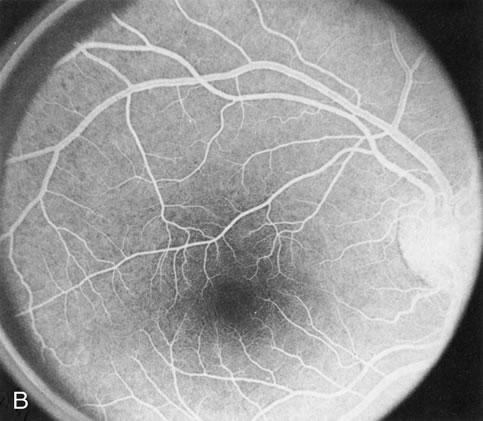

When the macula has typical superficial linear plications radiating from the fovea seen with schisis (e.g., juvenile retinoschisis, Goldmann-Favre disease), FA is normal (Fig. 8A and B). This indicates that the pathology is in the inner retina (probably Henle's fiber layer, considering the spokewheel pattern). However, when the schisis flattens, it is not uncommon to see a transmitted hyperfluorescence suggesting a secondary atrophy to the RPE (Fig. 8C and D).

Fig. 8. Juvenile XLR retinoschisis. The superficial macula schisis (A) does not affect the angiogram (B) except in a few areas where it has flattened and resulted in some pigment dispersion. When the macular schisis has entirely flattened (C) there is a mild transmission hyperfluorescence (D). At this stage the diagnosis can be suspected by the presence of an inferior retinoschisis (present in half) and confirmed by the typical electroretinographic finding of a scotopic electronegative response (present in all affected males).

The periphery may show schisis or vascular sheathing. Histopathology of the peripheral schisis in juvenile retinoschisis documents a splitting of the nerve fiber layer.13 FA shows retinal vascular abnormalities, including capillary nonperfusion, focal and diffuse vascular leakage, and intraretinal neovascularization, in many of these disorders.14 These may or may not be associated with schisis.

As with generalized tapetoretinal dystrophy (RP), FA clearly delineates retinal vascular decompensation in some of these patients. What remains to be answered is whether this is part of the basic disease process or a secondary reaction to it.